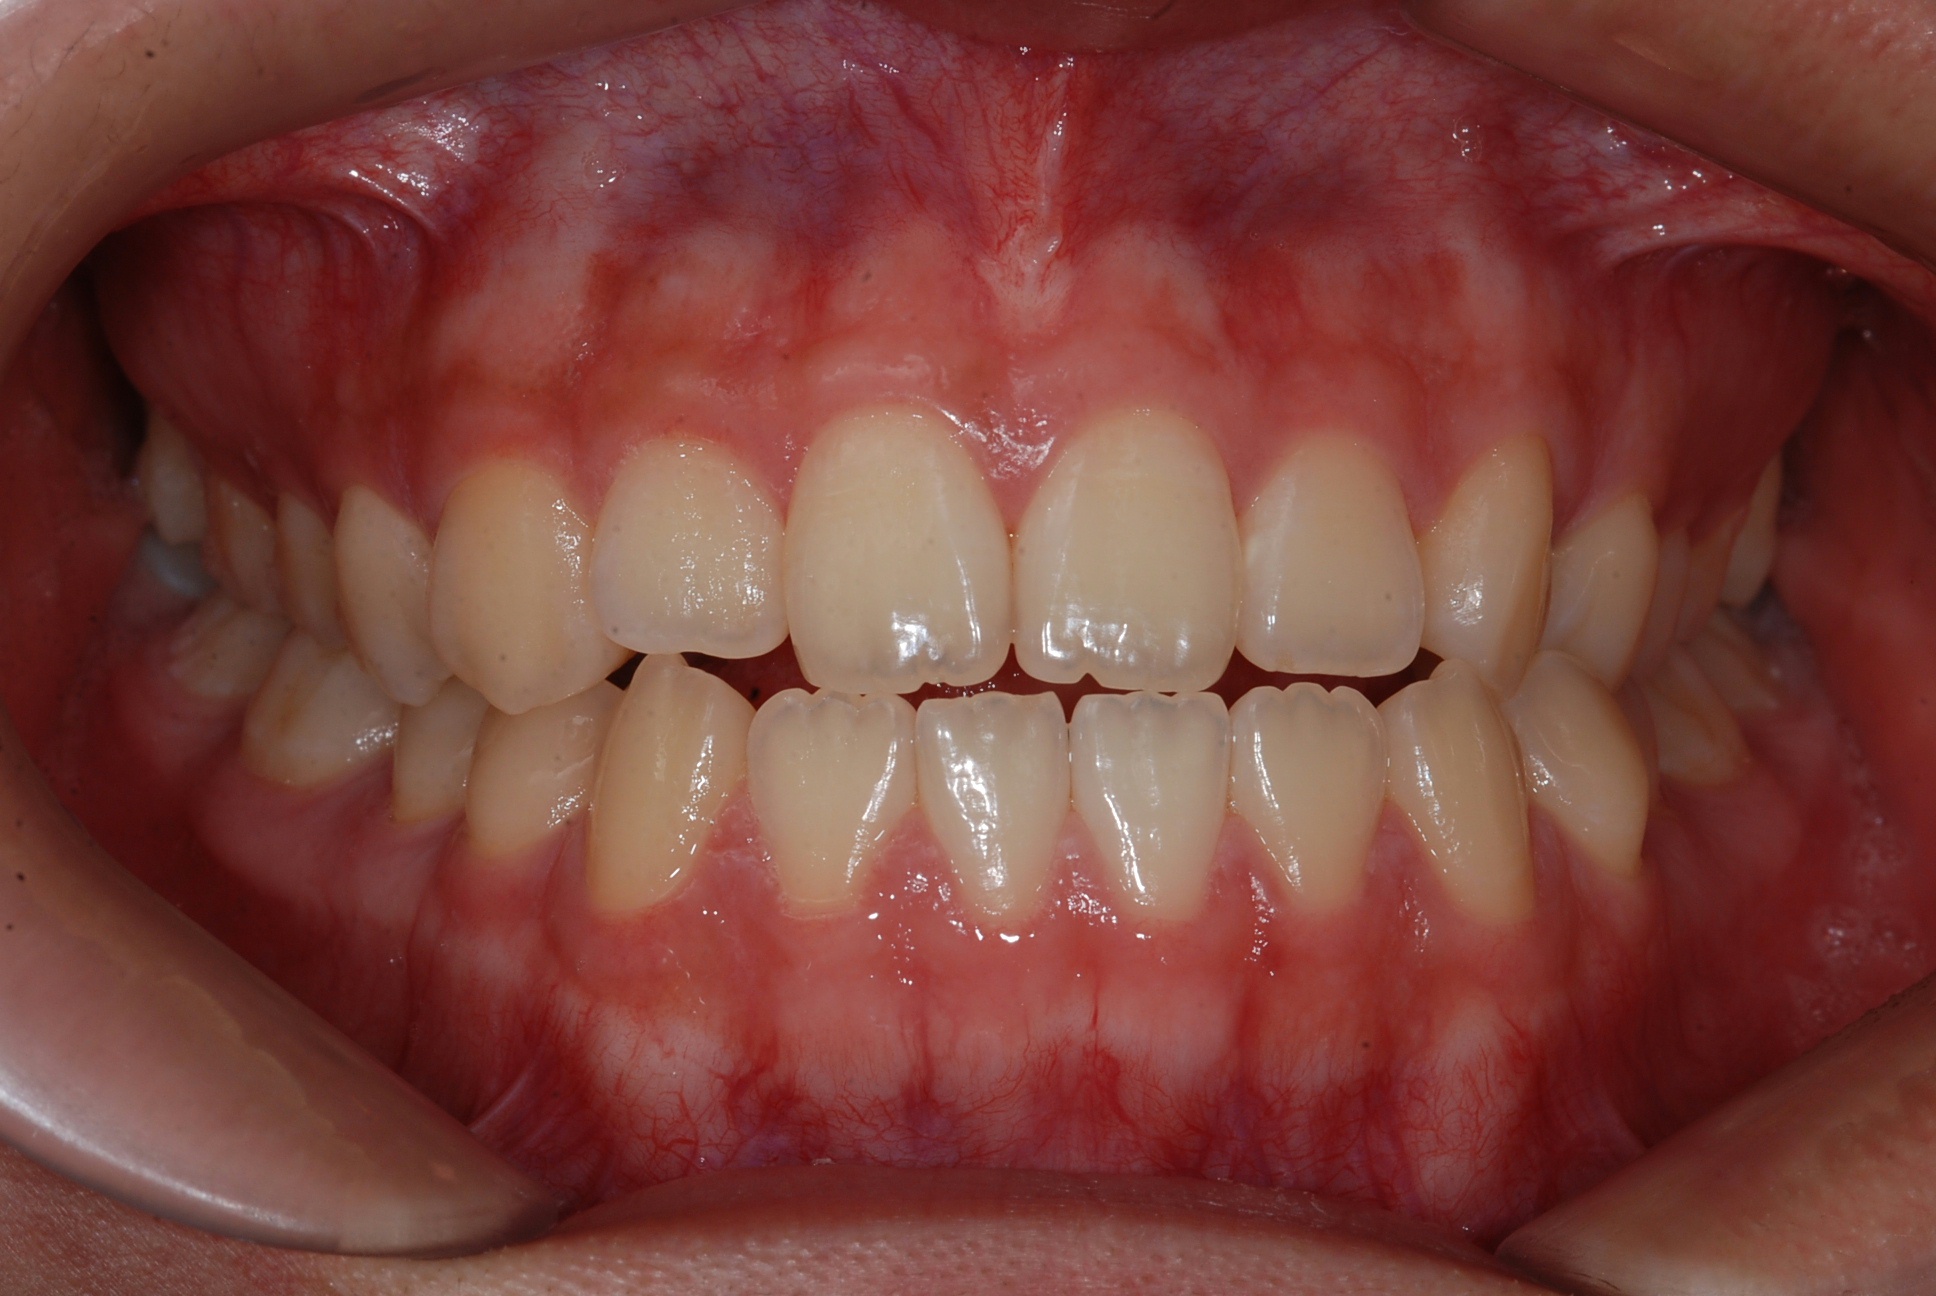

치료 후 사진입니다.